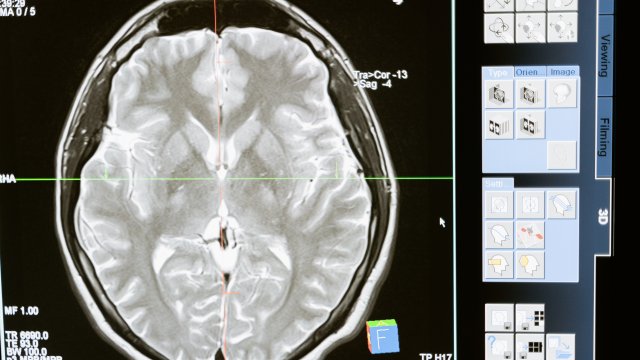

Проучването ще използва робот за хирургично поставяне на имплант в част от мозъка, която контролира намерението за движение, обяви Neuralink, добавяйки, че първоначалната му цел е да позволи на хората да контролират компютърен курсор или клавиатура, използвайки мислите си.